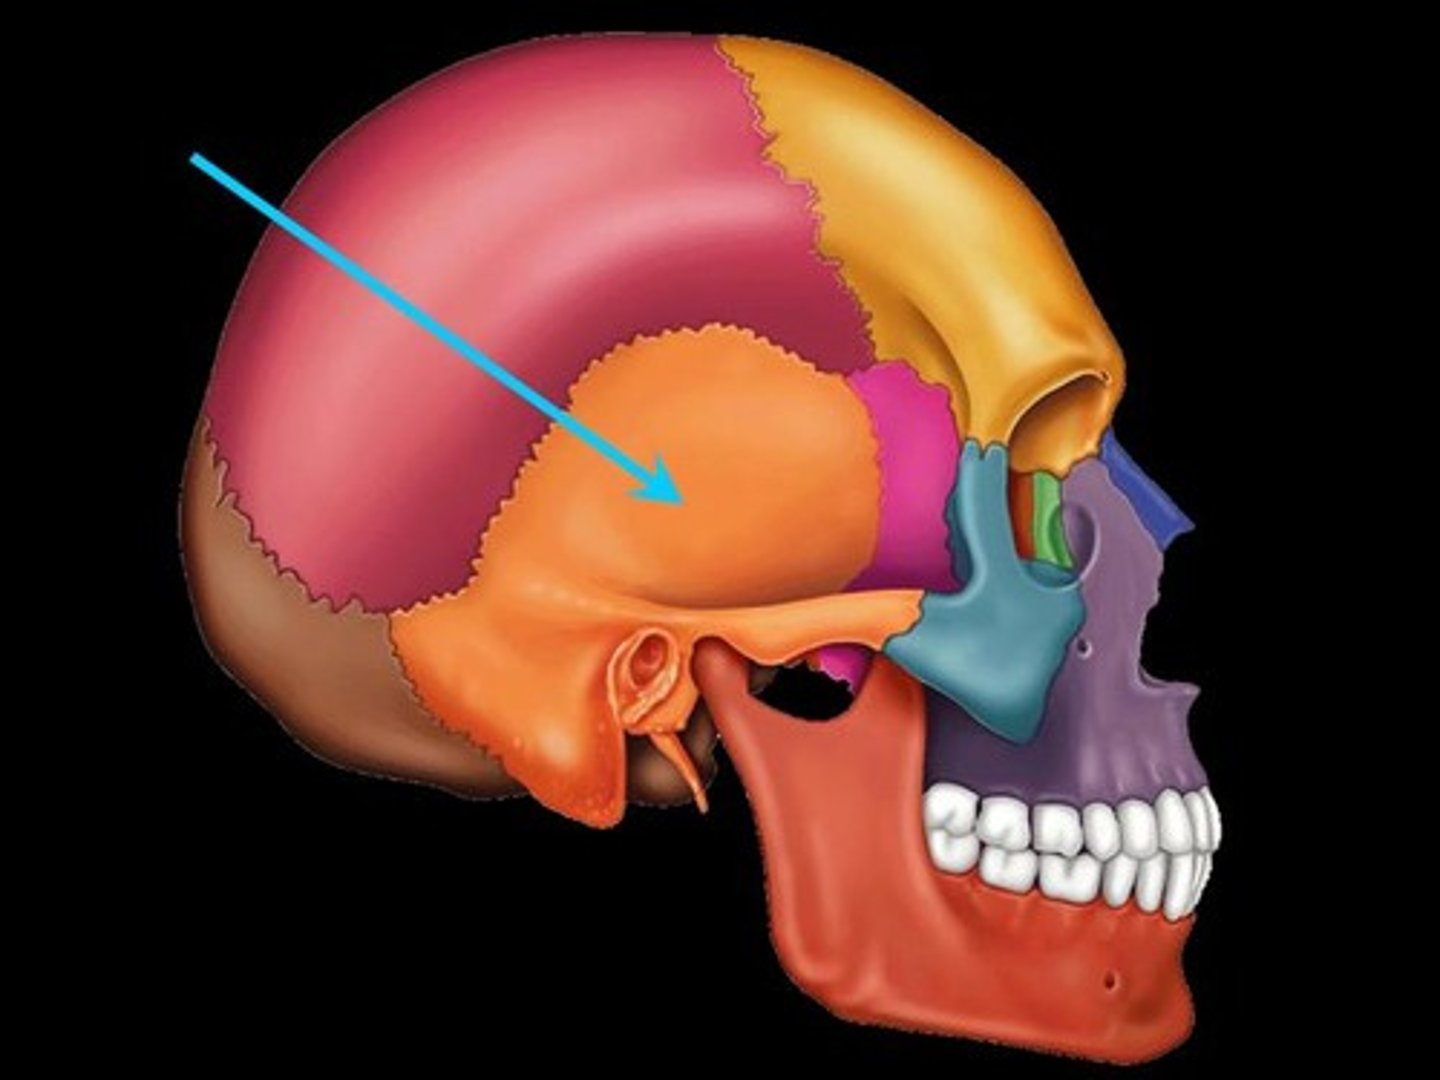

Parts of the Skull

Temporal Bone